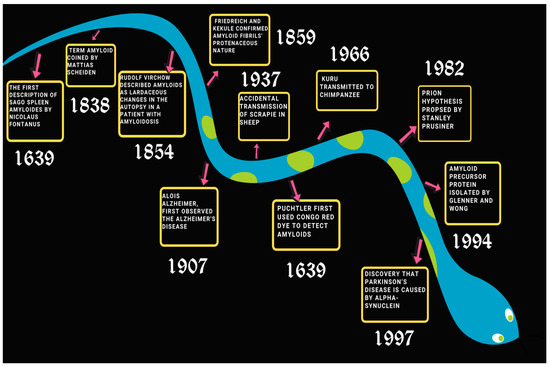

IJMS, Free Full-Text